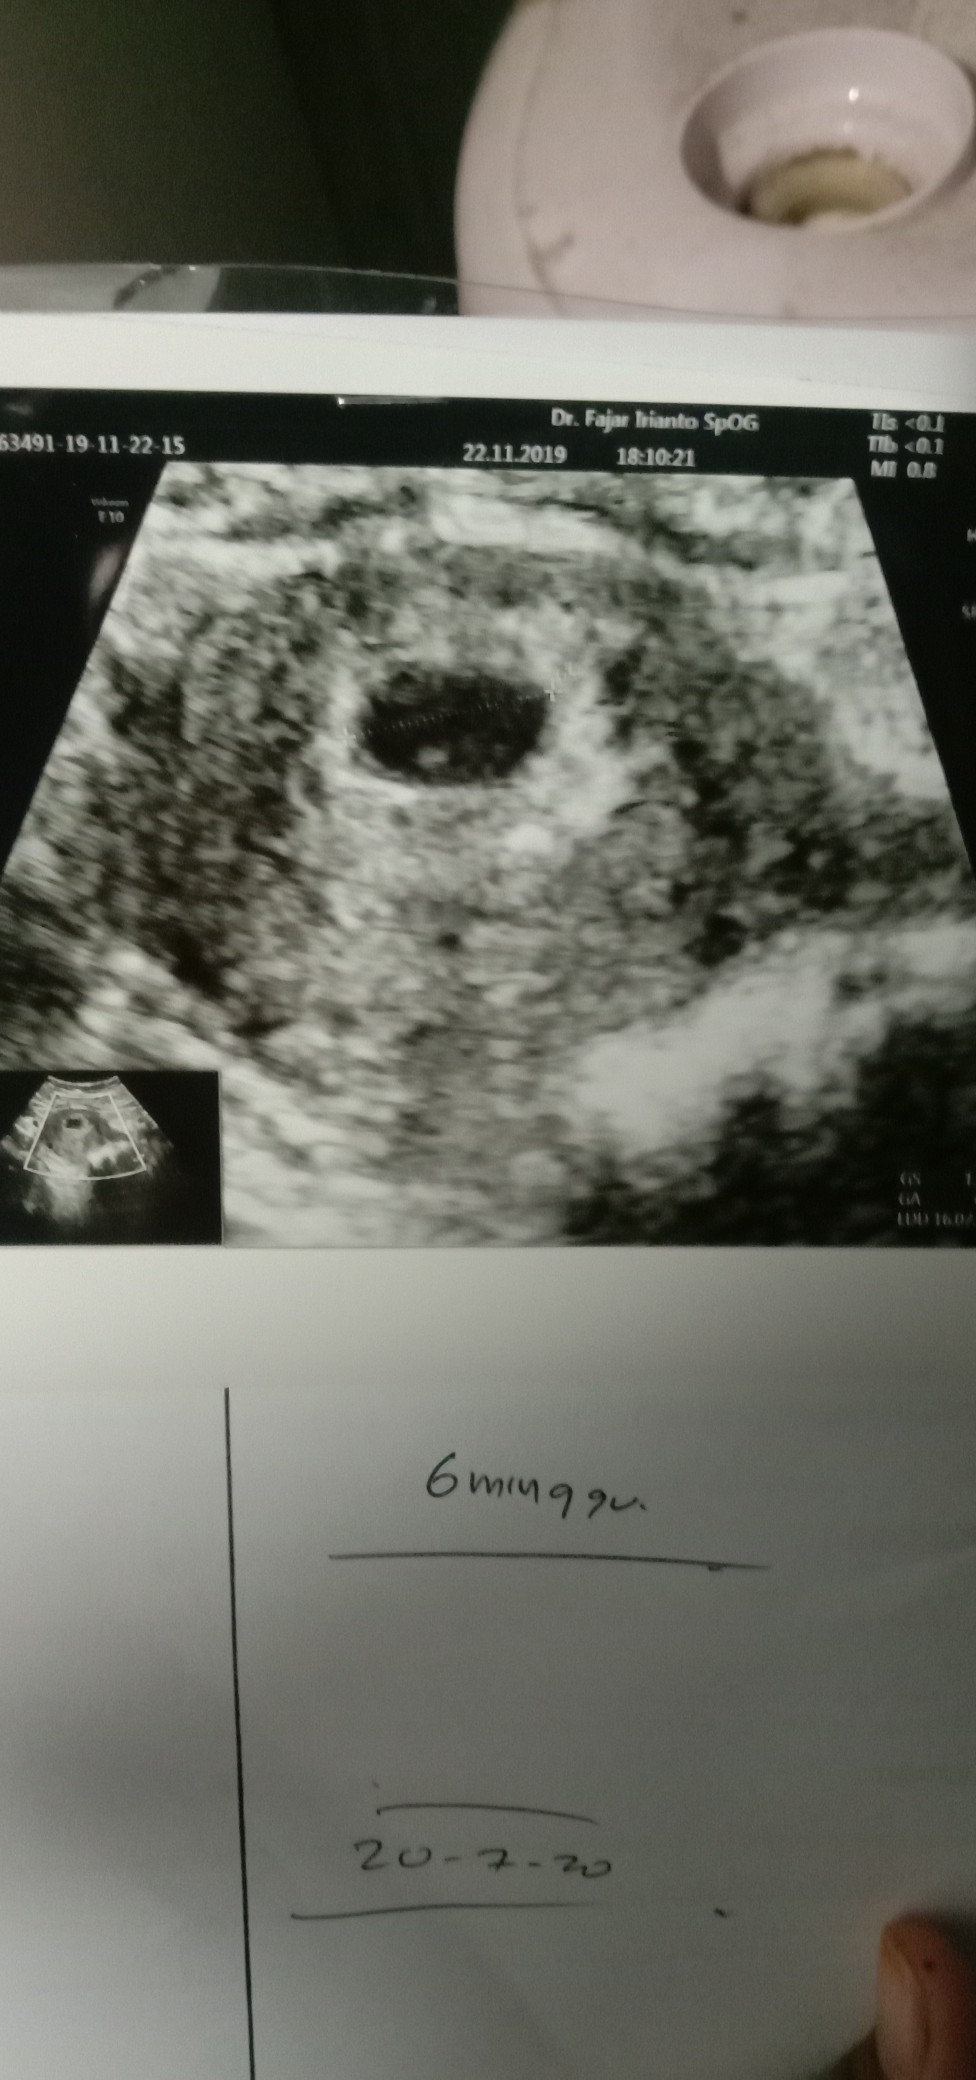

6 Minggu belum berkembang

Bun, ada yg punya pengalaman yg sama tidak sama kaya aku, kemarin aku usg usia kehamilan aku 6 minggu tapi dokter baru lihat kantung rahim aku aja belum ada perkembangan apa apa dilihat dua minggu lagi. apa memang seperti itu ya bun 6 minggu baru ada kantung rahimnya aja ? saya takut kejadian seperti kehamilan pertama BO

Ini hasil USG saya pas 6 Minggu Bun masih berbentuk kantong blm terlihat janin nya yg penting vitamin dari bidan/dokter rajin di minum insyaallah umur 10minggu udh terlihat janin nya ko bun